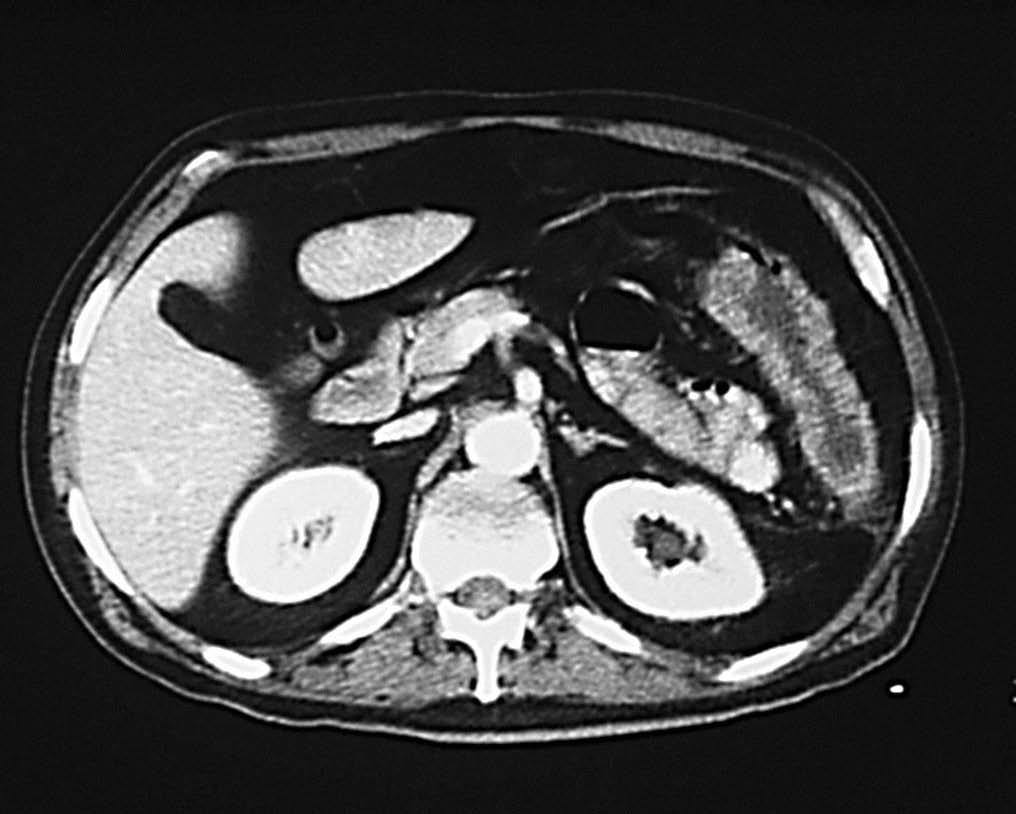

Desde el punto de vista tomodensitométrico (fig. 12) y de la RM los criterios semiológicos son más o menos similares: el engrosamiento mural y la hiperemia característica de una situación inflamatoria activa. Se describe el hecho de que el engrosamiento mural del colon suele ser más marcado en la colitis granulomatosa que en la ulcerosa, lo mismo que la irregularidad de los contornos, que suele ser también más acentuada en los casos de colitis granulomatosa.

Fig. 12.--Enfermedad de Crohn. A) La tomografía computarizada (TC) muestra la afectación del colon de carácter segmentario.(B) En la reconstrucción en plano coronal (MPR) puede apreciarse el marcado engrosamiento mural del colon descendente.